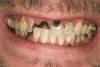

Joe soon learned how to manufacture the drug. His need for meth soon consumed his every thought. He basically lived to do more meth. He admitted that he had made some poor choices. Unfortunately once the addiction kicked in, he no longer had a choice, he had to use. This was his end result (Figure 4 through Figure 6). From these photographs, one might think that he had used the drugs his entire life; however, this progression happened over the course of only about 1 year of smoking the drug. Because of the caustic chemicals (muriatic acid, hydrochloric acid, lithium, etc) his teeth started to blacken, then break.

When Joe was finally arrested, his teeth were in the state seen in Figure 4 through Figure 6. He entered rehab, then served his time in prison. He received no dental treatment in prison. Once he was released on probation, he found it quite difficult to find a job. He was hired as a mechanic but only allowed to work in the garage. He was to have no contact with the customers because his appearance was hideous. His self-esteem was at the lowest point it could be. He felt better in prison. At least there, his prison mates understood why his teeth looked the way they did; many people in prison are there as a result of a chemical dependency issue.

As a new patient, Joe was instantly likable. He had a great sense of humor. He regretted how his life had turned out. When he finally presented to this author’s practice he was 24 years old. He wanted to remove the evidence of his addiction that were visible to anyone that came in contact with him. His teeth were totally destroyed by his drug use. There was no hope of saving any of them. There were horrible infections in his jaw bones that were spreading through his system. His only option was to remove all of his teeth and have dentures made. Impressions were taken with alginate. A bite was established in maximum intercuspation. We decided that his preoperative incisal edge positions of teeth Nos. 9 and 10 were adequate to recreate the incisal edge position in full dentures.

Figure 5  PRESENTATION CONDITION By the time Joe presented for treatment after serving time in prison and going to rehab, his teeth were completely destroyed by rampant decay. Although some teeth could have been saved, the patient chose to have all of the remaining teeth extracted in order to receive a set of full dentures.

Figure 5

Figure 6  PRESENTATION CONDITION By the time Joe presented for treatment after serving time in prison and going to rehab, his teeth were completely destroyed by rampant decay. Although some teeth could have been saved, the patient chose to have all of the remaining teeth extracted in order to receive a set of full dentures.

Figure 6